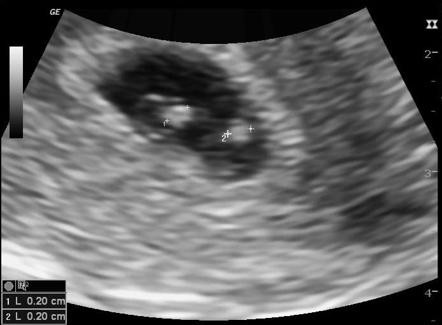

Các cặp sinh đôi hay sinh ba thường có tỉ lệ chết non hoặc tử vong trẻ sơ sinh cao hơn trẻ sinh một nên các bà mẹ mang đa thai thường được khuyên nên sinh sớm để giảm bớt nguy cơ này. Nhưng cho đến nay thời điểm tốt nhất để các cặp sinh đôi hoặc sinh ba có thể chào đời vẫn chưa được xác định.

Một nhóm nghiên cứu gồm nhiều nhà khoa học đến từ nhiều nước đã thực hiện 32 nghiên cứu trên 35.000 cặp sinh đôi tại để xác định thời gian chào đời tốt nhất đối với đa thai.

Nghiên cứu cho thấy các cặp sinh đôi khác trứng nên chào đời vào tuần 37 vì chỉ muộn hơn 1 tuần là tỉ lệ tử vong trẻ sơ sinh sẽ tăng thêm 8,8%.

Đối với những trường hợp song thai cùng trứng tức cùng hợp tử thì chưa có bằng chứng nào cho thấy sinh trước 36 tuần là tốt.

Vì vậy kết luận được đưa ra là để giảm thiểu tỉ lệ tử vong chu sinh, nếu không có biến chứng nào, các cặp sinh đôi khác trứng nên chào đời khi được 37 tuần, còn sinh đôi cùng trứng thì nên xem xét đẻ ở tuần thứ 36.

Vì nguy cơ tử vong trong các trường hợp đa thai luôn cao hơn đơn thai nên bất kỳ thông tin nào mới để có thể giảm nguy cơ này đều được đánh giá rất cao. Hơn nữa nghiên cứu này có quy mô khá lớn và kết quả cũng đáng chú ý.

Mang đa thai là đánh cược với tính mạng của cả mẹ và con vì có quá nhiều nguy cơ có thể xảy ra trong thai kỳ. Vì vậy cần theo dõi sát sao hơn để chẩn đoán sớm và xử lý kịp thời các biến chứng. Các bà mẹ nên chủ động hỏi ý kiến bác sĩ cũng như cân nhắc lợi ích và nguy cơ khi lựa chọn biện pháp và thời điểm sinh đẻ.